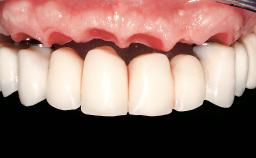

A 63-year-old female patient was referred to the University Medical Center in Groningen, Netherlands, for dental implant treatment. The patient had been edentulous in the upper jaw for 20 years. The remaining teeth in the lower jar had been removed two years before the consultation. The patient was wearing her first maxillary denture and her second mandibular denture; the latter was 1 year old at the time. The conventional upper denture had functioned satisfactorily for many years, but the patient complained about reduced stability and insufficient retention of her lower conventional denture. Her medical history revealed no significant findings. The intraoral examination revealed minor resorption of the maxillary alveolar process and extreme resorption of the mandibular alveolar process.

Prosthesis Type | RDP |